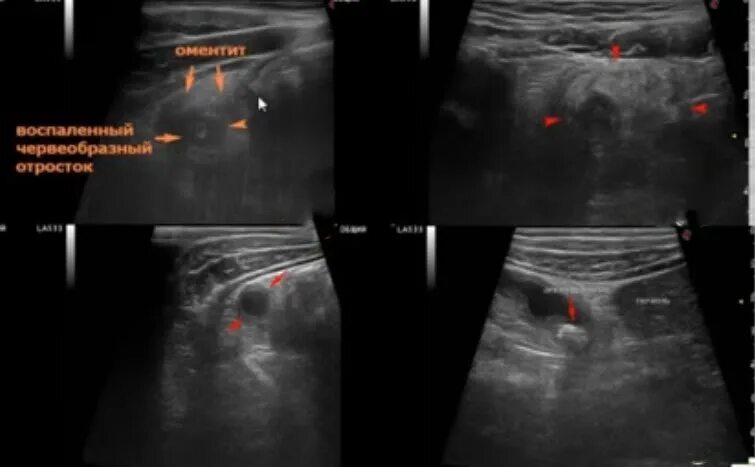

Осмотр при аппендиците